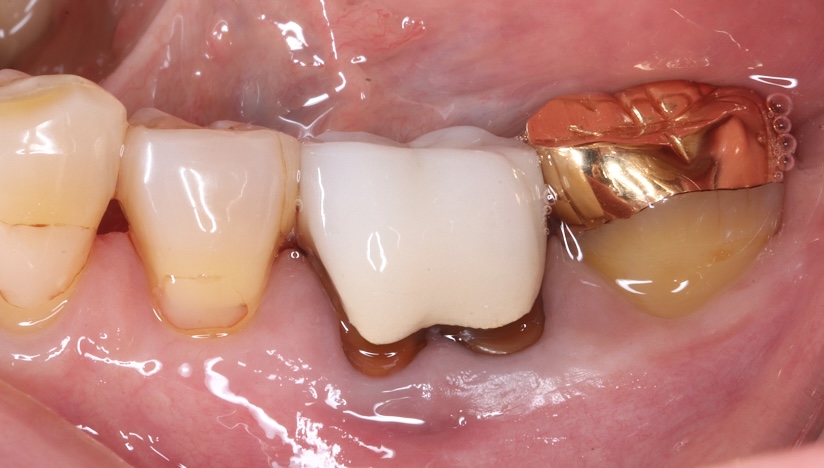

主訴

噛むと痛い、歯茎が腫れてきた

治療内容

抜歯即時インプラント埋入、リッジプリザベーション(顎堤温存術)

治療期間

6〜8ヶ月

治療費用

649,000

治療の

リスク

オッセオインテグレーションが得られなかった場合、撤去、再度埋入の可能性